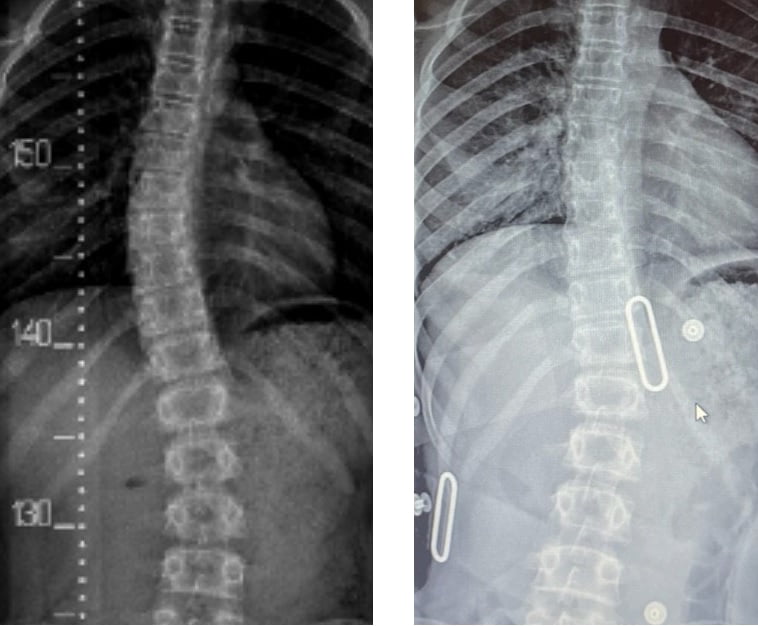

حتى أولئك الذين يعانون من اعوجاج العمود الفقري الشديد، حيث تزيد زاوية كوب عن 40 درجة، فقد استجابوا جيدًا لطريقه العلاج التي تعتمد على أحزمه الجنف تشينو-جينسينجن وبرنامج العلاج الطبيعي الذي يتبع مبادئ العلاج الطبيعي في شروث.

قبل و بعد

قبل و بعد